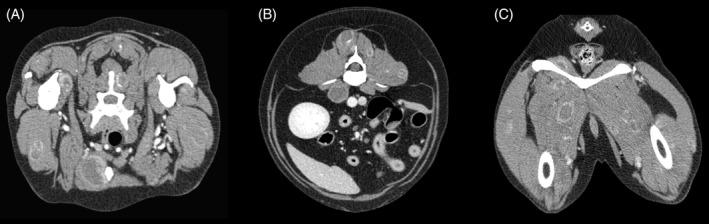

Retrospective study. Dogs with a final diagnosis of visceral or muscular HSA that underwent whole body CT scan were enrolled in the study. Final diagnosis of primary tumor and SMMs was reached by histology, cytology, or both. Signalment, clinical signs, localization of the primary lesion, and metastases characteristics were reviewed.

Sixty-one dogs met the inclusion criteria. Skeletal muscle metastases were detected in 15 dogs (24.6%) and all of these dogs had also metastases in ≥1 sites. Presence of SMMs was significantly higher in males but was not significantly related to age, neuter status, breed, localization, and dimensions of the primary tumor. Nine of 15 (60.0%) dogs with SMMs showed lameness or reluctance to move whereas these signs were not recorded in any of the 42 dogs without SMMs (P < .001).

Prevalence of SMMs in our population of dogs with HSA was higher in comparison to previous studies in the human and veterinary medical literature. Whole body CT is recommended for staging of dogs with HSA, because SMMs could be missed by clinical examination and traditional diagnostic imaging modalities.